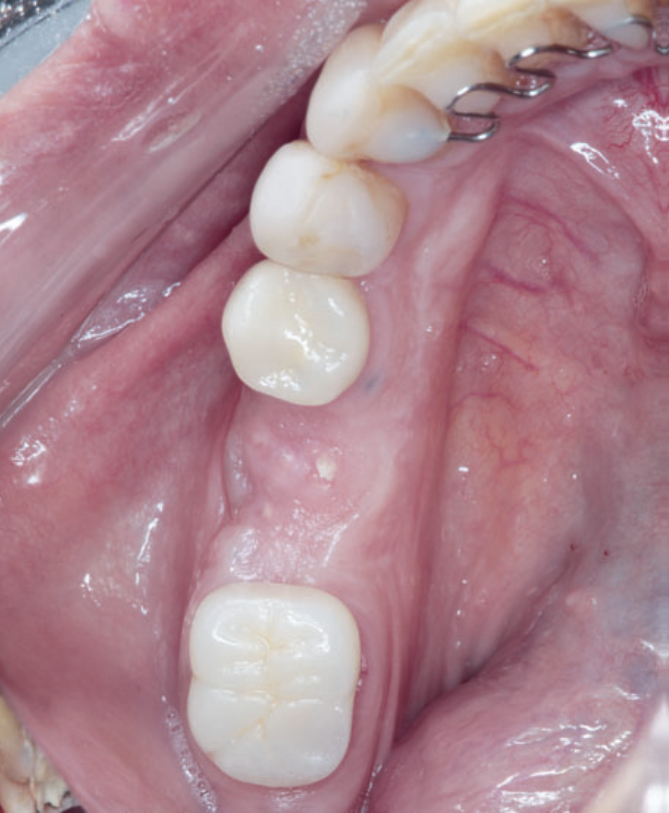

Neste relato de caso, a remoção da membrana Cytoplast foi feita aos 15 dias do pós-operatório. Depois de 23 dias, foi realizado o acompanhamento da cicatrização local (Figuras 11 e 12). Seis meses depois, a paciente voltou para realizar a reabertura da área cirúrgica (Figura 13) e retirada do parafuso de cobertura, visando à fase da reabilitação protética. Após a reabertura e remoção do parafuso de cobertura (Figura 14), e uso do Túnel Check para prótese cone-morse (estojo protético Implacil De Bortoli), foi selecionado o cicatrizador com dimensões de 4,5 mm x 5,5 mm (Figura 15) para guiar o condicionamento gengival (Figura 16). A reabilitação protética ainda está em andamento para finalização do caso (Figura 17).